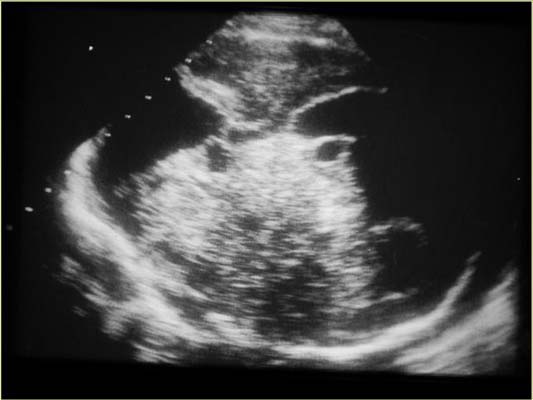

Tératume IC